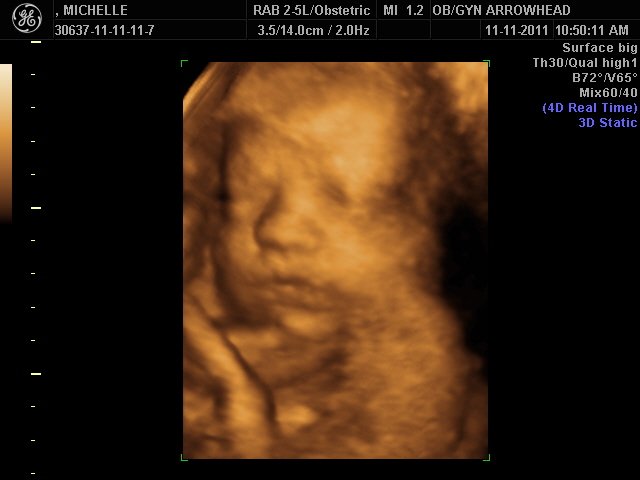

We offer complimentary 3D/4D Ultrasounds to all our OB patients around 30 weeks! The following photos are some examples of our work, shown with permission from our patients.